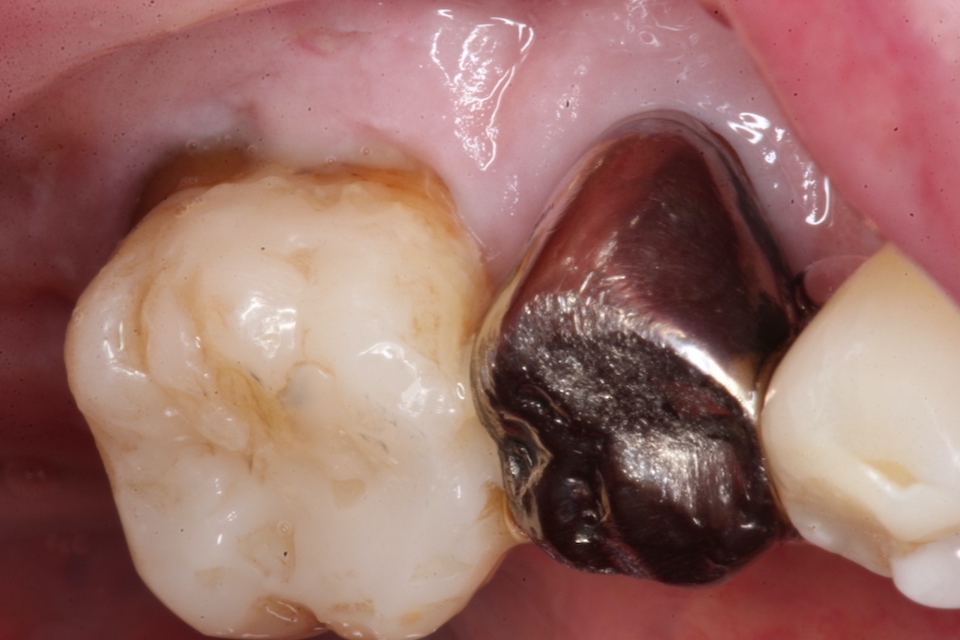

今日の抜歯再植術シリーズ39.1 2025.11.14

今日の抜歯再植術シリーズ39.0 2025.11.13

今日の抜歯再植術シリーズ38.3 2025.10.14